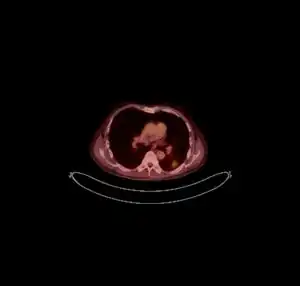

FDG PET/CT - Multiple nodules (some cavitating) in the left lower lobe

Pulmonary cryptococcosis has a worldwide distribution and is commonly underdiagnosed due to limitations in diagnostic capabilities. Since pulmonary nodules are its most common radiological feature, it can clinically and radiologically mimic lung cancer, TB, and other pulmonary mycoses. The sensitivity of cultures and the Cryptococcal (CrAg) antigen with lateral flow device on serum are rarely positive in the absence of disseminated disease.[15] Moreover, pulmonary cryptococcosis worsen the prognosis of cryptococcal meningitis.[15]